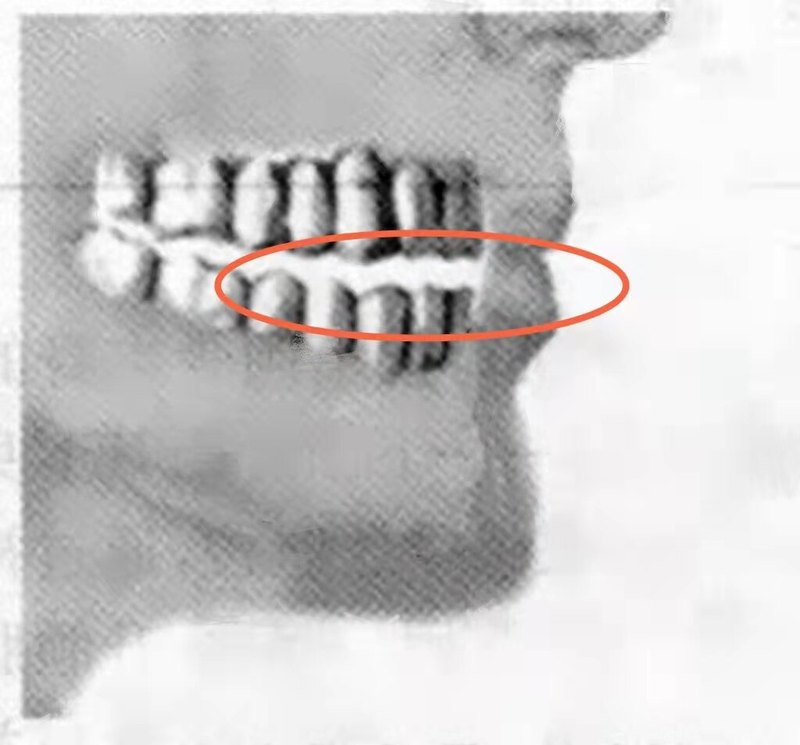

顳下頜關(guān)節(jié)紊亂病的常見癥狀一般主要癥狀是張口障礙、疼痛、異響。為了方便醫(yī)生了解您的病情,最好能提供以下信息:1、主要的癥狀是疼痛、張口受限、彈響的其中哪一種?或者哪幾種?多長時(shí)間了?2、自己覺得近期疾病的發(fā)生或者變嚴(yán)重是由于什么原因?3、已經(jīng)做過什么評(píng)估或者治療?結(jié)果如何?效果如何?4、提供張閉口、左右側(cè)移下巴的正面視頻;側(cè)面張口到最大的視頻(頭面部都要顯示)5、想讓醫(yī)生提供什么幫助和答疑?6、顳下頜關(guān)節(jié)的核磁共振是必備的影像學(xué)檢查,問診時(shí)請(qǐng)?zhí)峁﹫D像。(可以不用文字報(bào)告)。個(gè)別骨性問題,還需要cbct。

休息位,指息止頜位,除吞咽、咀嚼、說話以外的時(shí)間,下頜所處的位置,肌肉都應(yīng)該是放松的狀態(tài)。具體操作:1、上下門牙先對(duì)刃,然后微微分開2-3mm,后縮2mm,讓牙齒不咬在一起。2、嘴唇微微閉上,嘴唇會(huì)自動(dòng)被黏住。3,咽一下口水,然后放松舌頭,它會(huì)像吸飽水的海綿一樣膨脹開,就像吸盤一樣吸附上顎(不是用力抵上鄂),維持上下頜的距離。舌尖的位置因人而異,可以放在牙齒后面??s脖子至微微出現(xiàn)雙下巴,臉部肌肉放松,用鼻子呼吸。要借助表面皮膚的張力、嘴唇唾液的粘力、咽口水制造的口腔負(fù)壓、舌頭的吸附力等,替代咀嚼肌的發(fā)力,維持下頜的懸吊狀態(tài)與位置。做休息位時(shí),一定要先做到“休息”,再做到“位置”。如果是用力維持“位”而放棄了“休息”,那就是本末倒置了。習(xí)慣的養(yǎng)成需要1個(gè)月,所以別著急,慢慢來。顳下頜關(guān)節(jié)紊亂還與體態(tài)也有著莫大的關(guān)系。多數(shù)患者都有口呼吸、頭前伸、圓肩駝背,腰椎前突,骨盆前傾,甚至到足底的扁平足,需要從整體的角度治療這個(gè)疾病。